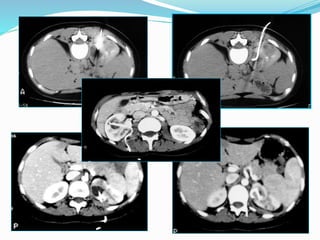

ΠΑΡΟΧΕΤΕΥΣΗ ΧΟΛΗΦΟΡΩΝ

Μέθοδοι τοποθέτησης:

.CT

.Υπερηχοτομογραφικά

.Ακτινοσκοπικά

.Συνδυασμοί

.Διεγχειρητικά